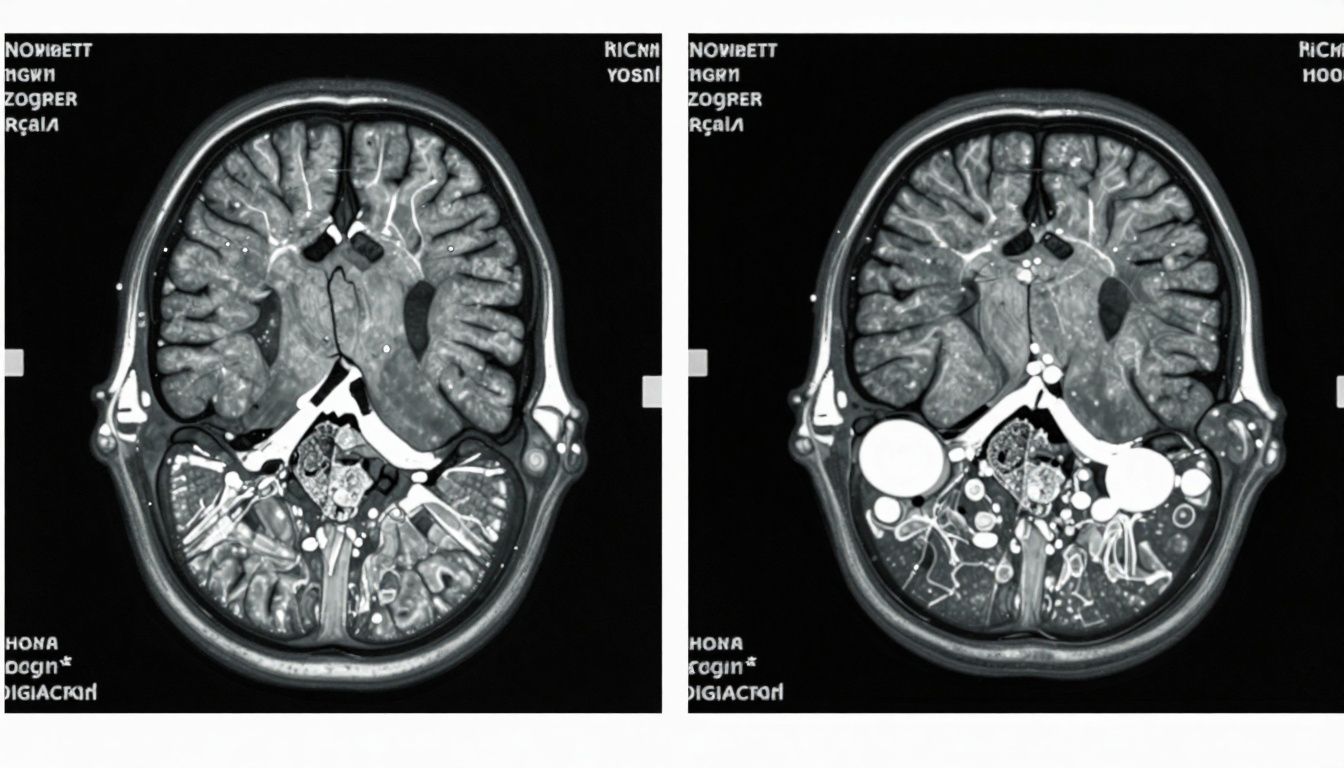

![]()

Epidemiology: How Common Is Neurodegeneration in Aging?

- Mild Cognitive Impairment (MCI): Affects up to 20% of people over 65.

- Alzheimer’s Disease: The most common dementia, affecting an estimated 10% of people over 65.

- Parkinson’s Disease & Other Disorders: Prevalence increases significantly with age, though they are less common than Alzheimer’s.

The risk of neurodegeneration rises with age, genetics (e.g., APOE4 status), and certain lifestyle factors.